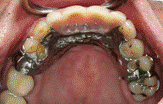

患者A先生

上顎 正面 下顎

患者B小姐

以上兩位患者口內狀況非常複雜,要制定一個好的治療計畫,

不只要考慮到患者的牙齒條件,

還要顧及患者意願、時間、金錢、評估可獲得的結果等等。

所以像這類型的Case 醫師通常在初步的溝通後會先做出一兩個不同的治療計畫,

再和患者解釋,了解患者接受程度。